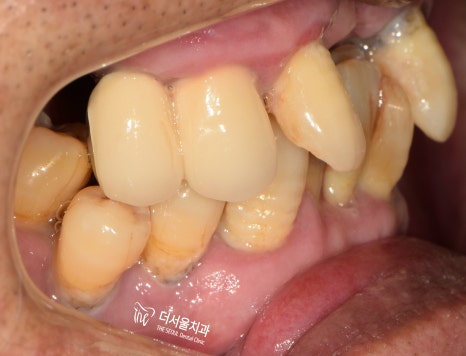

먼저 환자분 구내를 살펴보겠습니다.

상태가 너무도 좋지 않았습니다.

전체적으로 교합이 잘 이뤄지지 않고

윗니는 잇몸이 크게 부어있습니다.

게다가 많은 이가 흔들리고 있었구요.